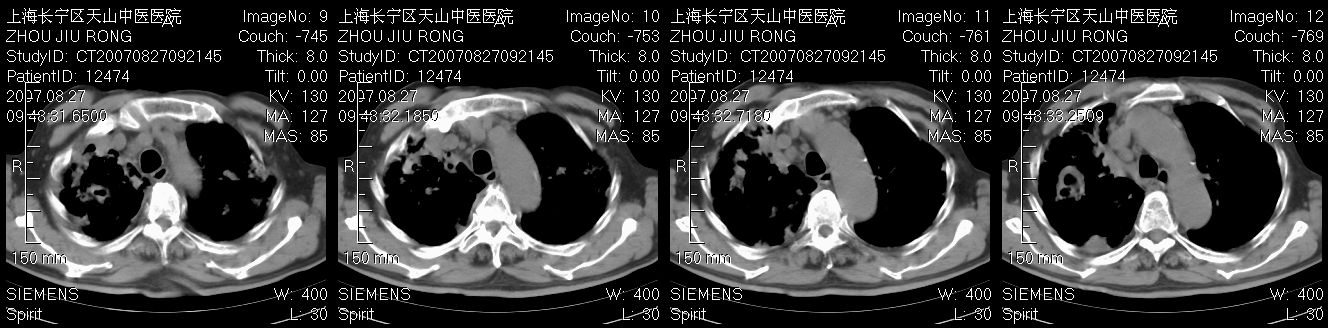

以下是引用zjzjr在2007-8-30 21:47:00的发言:[br]双肺弥漫性结节状、斑片状影,部分形成空洞,病灶以双肺上叶为著(符合结核发病部位),纵隔内见肿大淋巴结影。支持双肺继发性结核伴右上肺空洞形成。

以下是引用zjzjr在2007-8-30 21:47:00的发言:[br]双肺弥漫性结节状、斑片状影,部分形成空洞,病灶以双肺上叶为著(符合结核发病部位),纵隔内见肿大淋巴结影。支持双肺继发性结核伴右上肺空洞形成。

以下是引用gaoshengjiang在2007-8-31 10:24:00的发言:[br]双肺弥漫性斑片状影及多发空洞影,其间夹杂多量条索状影,胸膜肥厚、粘连并有结节状改变,纵隔多枚淋巴结肿大,考虑1双肺继发型肺结核合并感染?2韦格氏肉芽肿?[br] 支持!

以下是引用zjzjr在2007-8-30 21:47:00的发言:[br]双肺弥漫性结节状、斑片状影,部分形成空洞,病灶以双肺上叶为著(符合结核发病部位),纵隔内见肿大淋巴结影。支持双肺继发性结核伴右上肺空洞形成。

以下是引用zjzjr在2007-8-30 21:47:00的发言:[br]双肺弥漫性结节状、斑片状影,部分形成空洞,病灶以双肺上叶为著(符合结核发病部位),纵隔内见肿大淋巴结影。支持双肺继发性结核伴右上肺空洞形成。

以下是引用zjzjr在2007-8-30 21:47:00的发言:[br]双肺弥漫性结节状、斑片状影,部分形成空洞,病灶以双肺上叶为著(符合结核发病部位),纵隔内见肿大淋巴结影。支持双肺继发性结核伴右上肺空洞形成。